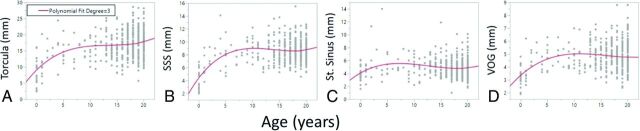

FIG 3.

Variations in venous size by age in the torcula (A), superior sagittal sinus (B), straight sinus (C), and vein of Galen (D). SSS indicates superior sagittal sinus; St. Sinus, straight sinus; VOG, vein of Galen.

To determine at which specific age the sinuses of the DVS system reached maximal diameter, we plotted the diameter of each sinus as a function of age. The plots are shown in Figs 3 and 4. The SSS, torcula, straight sinus, and VOG all reached maximal diameter by 7–10 years of age. Both the right and left transverse venous sinuses reached maximal size around 5–7 years of age. The left sigmoid sinus reached maximal diameter around 7–10 years of age, while the right sigmoid sinus reached maximal size around 12.5 years of age. The right and left internal jugular veins reached maximal size around 7–10 years of age.